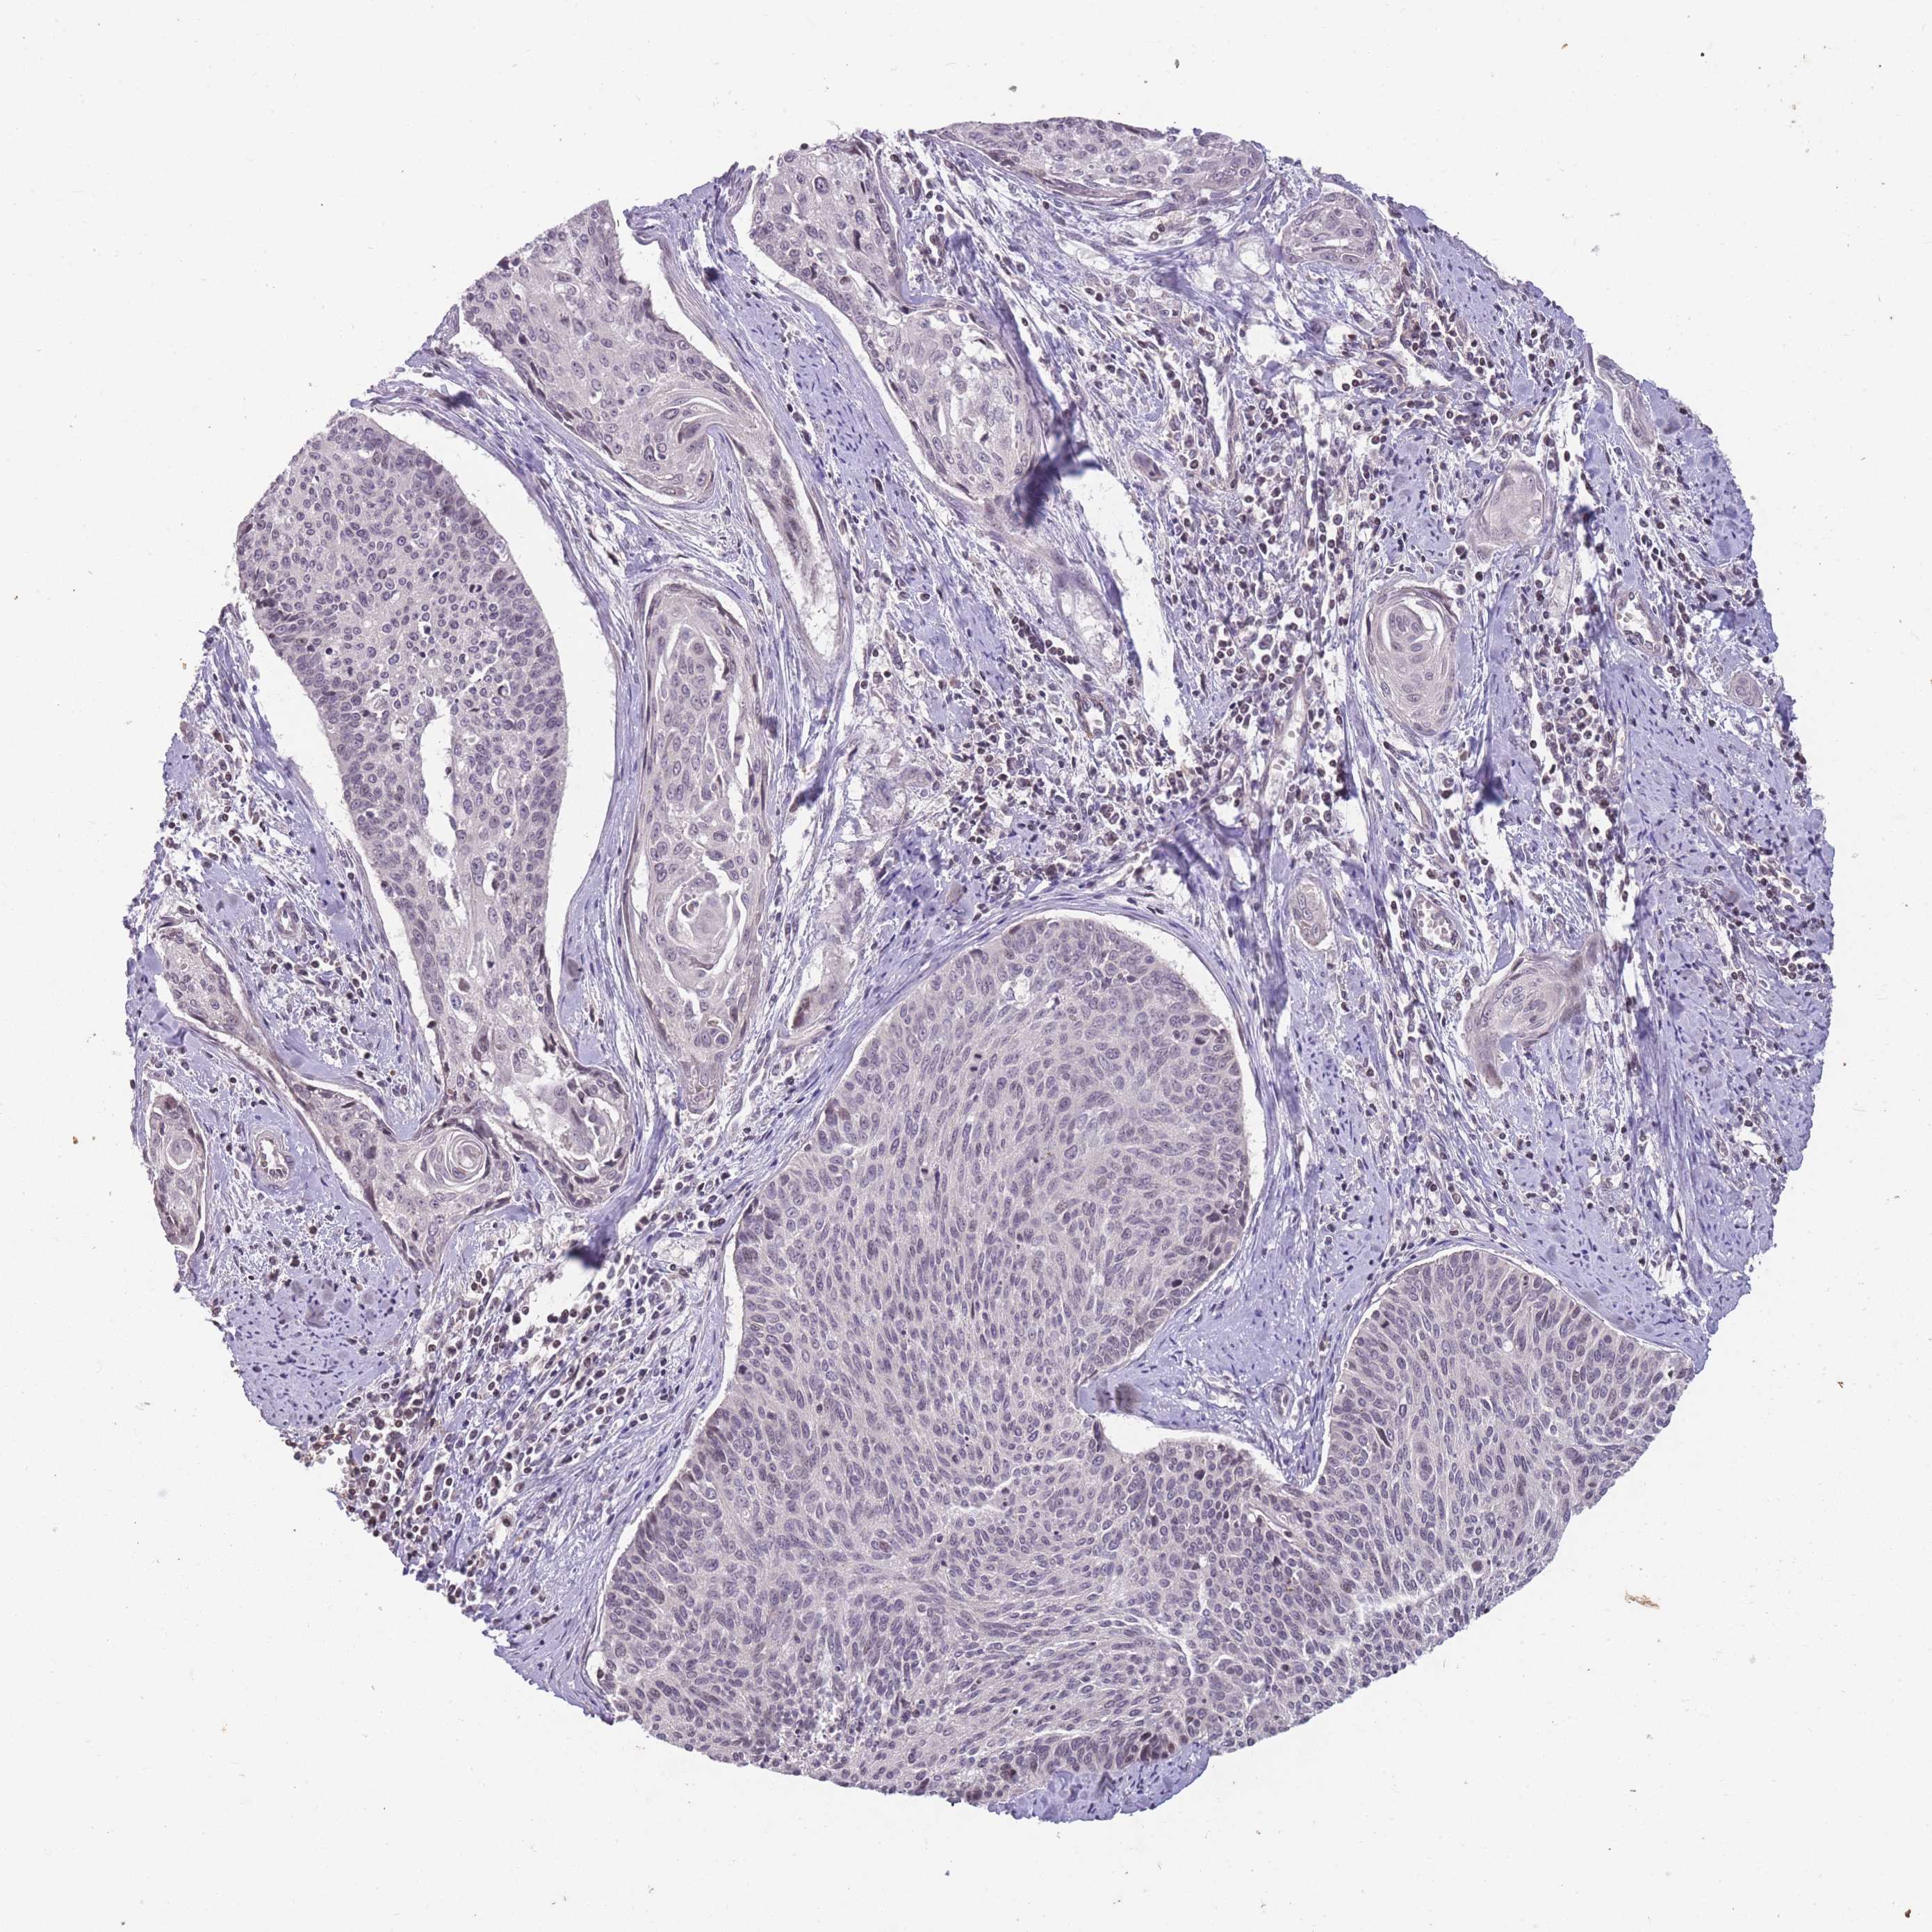

CERVICAL CANCER - Protein expressioni

A mouse-over function shows sample information and annotation data. Click on an image to view it in a full screen mode. Samples can be filtered based on level of antibody staining by selecting one or several of the following categories: high, medium, low and not detected. The assay and annotation is described here.

Note that samples used for immunohistochemistry by the Human Protein Atlas do not correspond to samples in the TCGA dataset.

Antibody stainingi

Antibody staining in the annotated cell types in the current human tissue is reported as not detected, low, medium, or high, based on conventional immunohistochemistry profiling in selected tissues. This score is based on the combination of the staining intensity and fraction of stained cells.

Each image is clickable and will lead to virtual microscopy that enables deeper exploration of all samples and also displays staining intensity scores, fraction scores and subcellular localization as well as patient and tissue information for each sample.

Antibody HPA008121

Antibody CAB032489

Squamous cell carcinoma, NOS

Adenocarcinoma, NOS